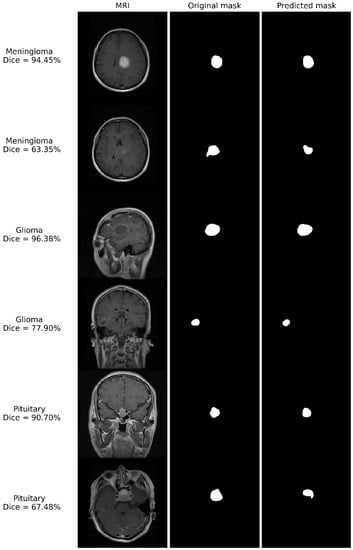

Some of the results of segmentation after training the network on the original data set with record-wise data division are shown in Figure 3. Examples of tumor segmentation with Dice coefficients higher and lower from its median value (83.31%) for each tumor type are presented, along with an MRI image and mask. The segmented images also show the Dice coefficient achieved for that segmentation. Even in the cases where the Dice coefficient is lower, the predicted mask clearly indicates the existence and position of the tumor, which shows the significant diagnostic value of our method.

Figure 3.

Examples of segmentation after training the network on the original dataset with record-wise data division. The original MRI image, mask, and segmented tumor are shown. The type of tumor, as well as the Dice coefficient achieved, are also indicated.